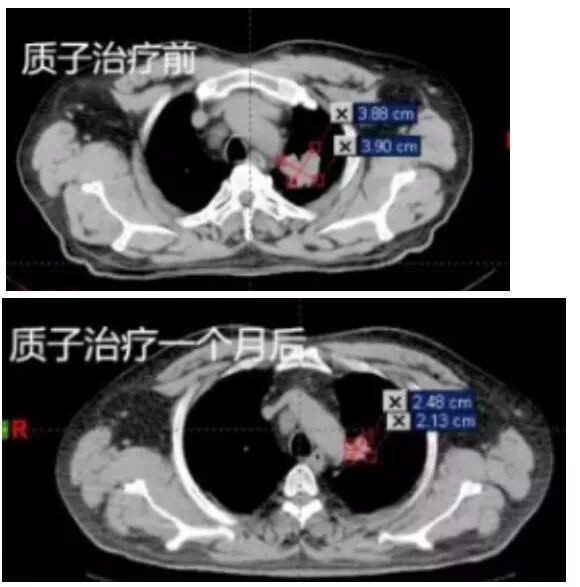

55岁男性,无明显诱因出现走路左偏,左侧上肢抽搐,发作时意识清醒,持续时间约1-2分钟,可自行缓解。PET-CT显示:左肺上叶尖后段肺癌;并右侧顶叶脑转移,在全麻下行“脑转移瘤切除术”,术后症状明显改善。

病理检测无基因突变,术后行化疗2周期,后拟行手术治疗,因肺部肿瘤靠近大血管,不能手术,经专家会诊,行质子放射治疗。质子治疗一个月后,肿瘤体积缩小65%。

质子治疗前后对比CT